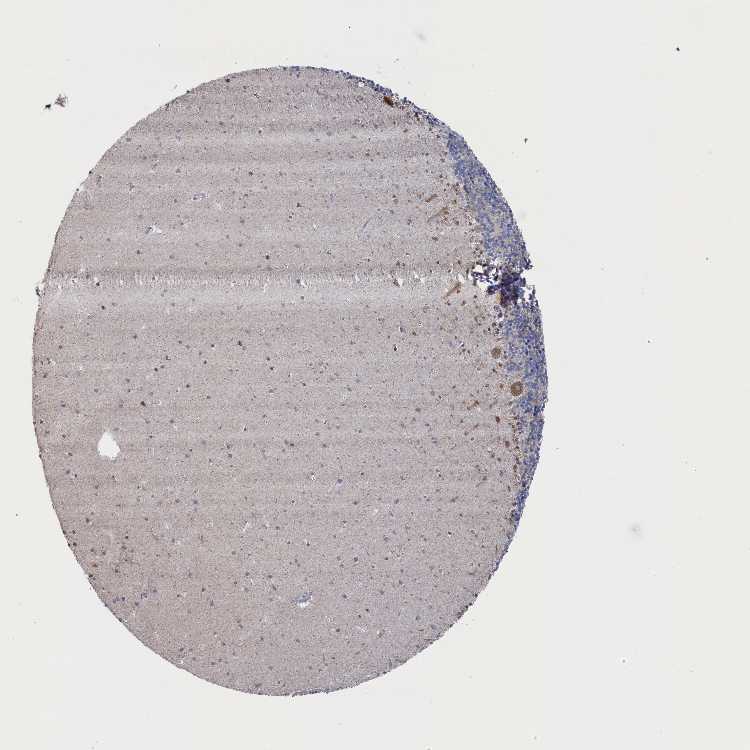

CEREBELLUM - Antibody stainingi

Antibody staining in the annotated cell types in the current human tissue is reported as not detected, low, medium, or high, based on conventional immunohistochemistry profiling in selected tissues. This score is based on the combination of the staining intensity and fraction of stained cells.

Each image is clickable and will lead to virtual microscopy that enables deeper exploration of all samples and also displays staining intensity scores, fraction scores and subcellular localization as well as patient and tissue information for each sample.

Antibody HPA043160

Purkinje cells Medium

Cells in granular layer Low

Cells in molecular layer Low